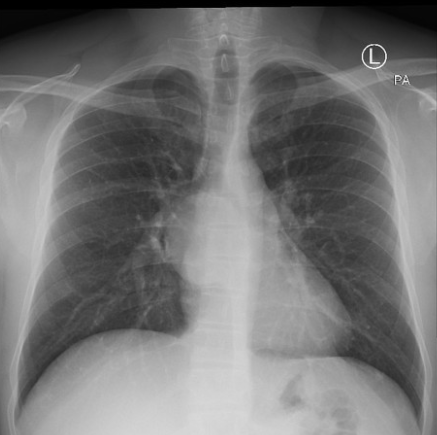

Unilateral hyperlucent lung

1. Poland syndrome

2. Mastectomy

3. Swyer james (obliterative bronchiolitis)

4. Scoliosis

Don;t forget pneumothorax. FB

PE can also give hyperlucent lung due to lack of blood flow